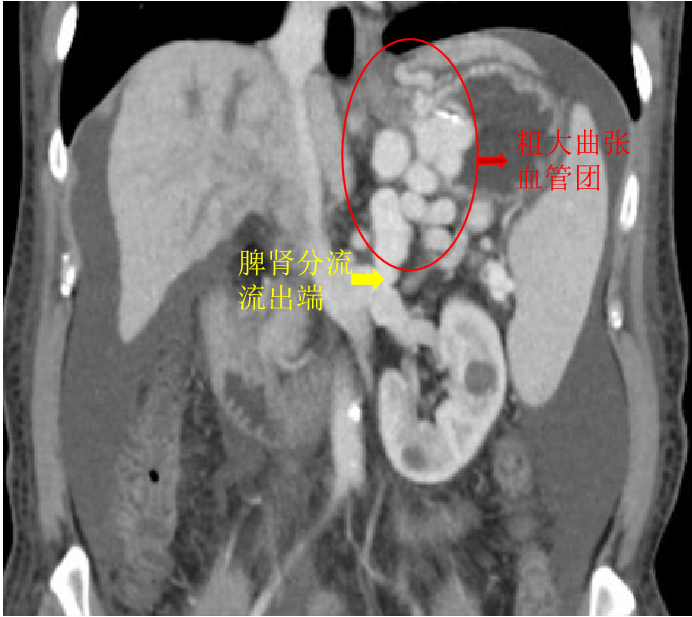

雪上加霜的是,患者门静脉CT血管造影术(CTA检查)示其除了胃静脉曲张还伴随着粗大的脾肾分流,这意味着针对胃静脉曲张出血普遍采取的手段——组织胶注射栓塞治疗,出现异位栓塞的风险将会显著增高,组织胶通过粗大的脾肾分流进入体循环,极易造成重要器官栓塞等严重并发症。

为实现胃底巨大曲张静脉的完全封堵,减少再发出血和异位栓塞的风险,消化内科与肝胆介入科共同研讨患者病情后,决定选择行改良球囊阻断分流道联合内镜下胃静脉曲张栓塞术,用球囊进行封堵有效避免了严重并发症的发生。